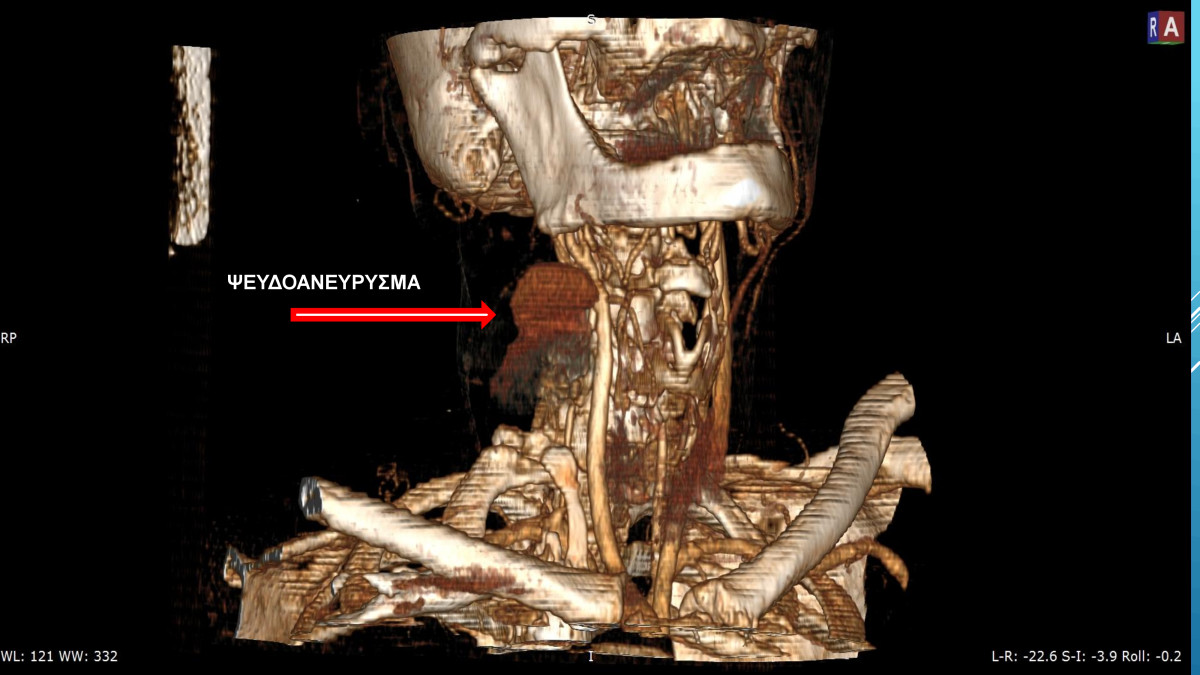

“Ενδαγγειακή Αποκατάσταση Ψευδοανευρίσματος Καρωτίδας μετα Ενδαρτηρεκτομή”

17ο ΠΑΝΝΕΛΗΝΙΟ ΣΥΝΕΔΡΙΟ ΑΓΓΕΙΑΚΗΣ & ΕΝΔΑΓΓΕΙΑΚΗΣ ΧΕΙΡΟΥΡΓΙΚΗΣ – ΑΓΓΕΙΟΛΟΓΙΑΣ

2018, Θεσσαλονίκη